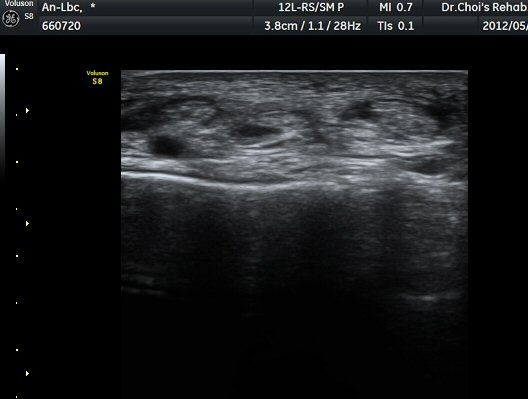

¹ß¸ñ ¾Õ Ⱦ´Ü¸é°Ë»ç¿¡¼­ Àü°æ°Ç(TA), ¾öÁö½ÅÀü°Ç(EPL), ¹ß°¡¶ô½ÅÀü°Ç(EDL)ÀÇ ºÎÁ¾ ¹×

°Ç ÁÖÀ§ ¼ö¾× Àú·ù°¡ °üÂûµÈ´Ù(»çÁø 1, 2). °ÇÀÇ ºñÈÄ¿Í ¼ö¾×Àú·ù´Â °ÇÃø(»çÁø 4)°ú ºñ±³Çϸé

¶Ñ·ÈÇÏ´Ù. Àü°æ°Ç Á¾´Ü¸é°Ë»ç¿¡¼­ °ÇÀÇ ºÎÁ¾°ú °Ç ÁÖÀ§ ¼ö¾× Àú·ù°¡ °üÂûµÈ´Ù(»çÁø 3). °ÇÀÇ

ºÎÁ¾°ú ¼ö¾×Àú·ù´Â °ÇÃø°ú ºñ±³ÇÏ¸é ¶Ñ·ÈÇÏ´Ù(»çÁø 5).¤·